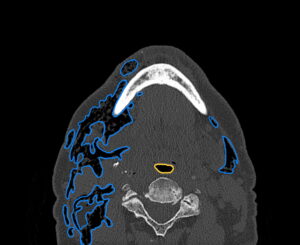

Dental Free Air CT Axial Annotated. JETem 2025